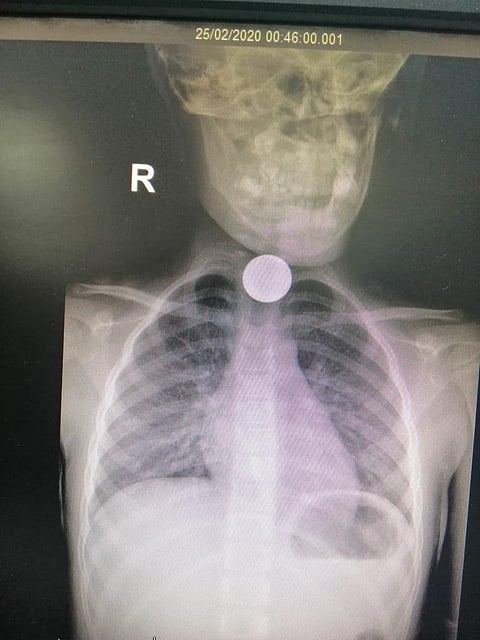

تعامل قسم طوارئ الأطفال بمستشفى الولادة والأطفال بنجران بنجاح مع حالة طفلة تعاني صعوبة في البلع؛ نتيجة بلع قطعة نقدية معدنية، وحدوث ازرقاق وإجهاد تنفسي، حيث تم إجراء الفحوص اللازمة، والتي أظهرت بالأشعة وجود جسم غريب، كما تم توقيع الكشف الطبي على الطفلة، وتبيّن وجود قطعة معدنية.

وقد تم إجراء منظار الشعب الهوائية واستخراج الجسم الغريب (قطعة معدنية) بنجاح بفضل الله وتوفيقه، تحت إشراف فريق طبي تمريضي مؤهل بالعمليات، مما أسهم في تحسن واستقرار حالة الطفلة وخروجها من المستشفى بصحة جيدة ولله الحمد.